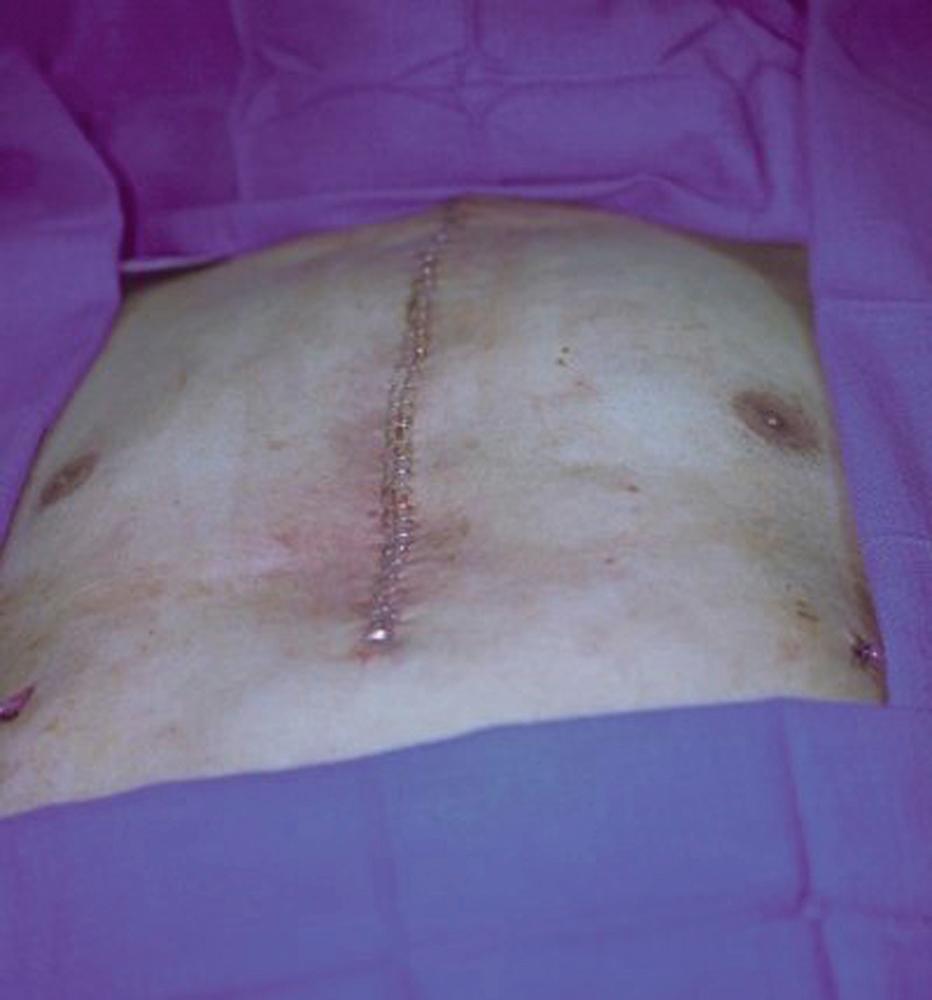

Both flaps were advanced and approximated in the midline of the sternal wound and final closure was performed in three layers after hemostasis and placement of a drain under each muscle flap. The muscle layer was approximated with interrupted 2-0 PDS sutures. The deep dermal layer was approximated with interrupted 3-0 Monocryl sutures. The skin closure was performed with skin staples ( Fig. 21.4 ).

Fig. 21.4, Intraoperative view showing the final appearance after bilateral pectoral major myocutaneous advancement flap for this sternal wound closure.